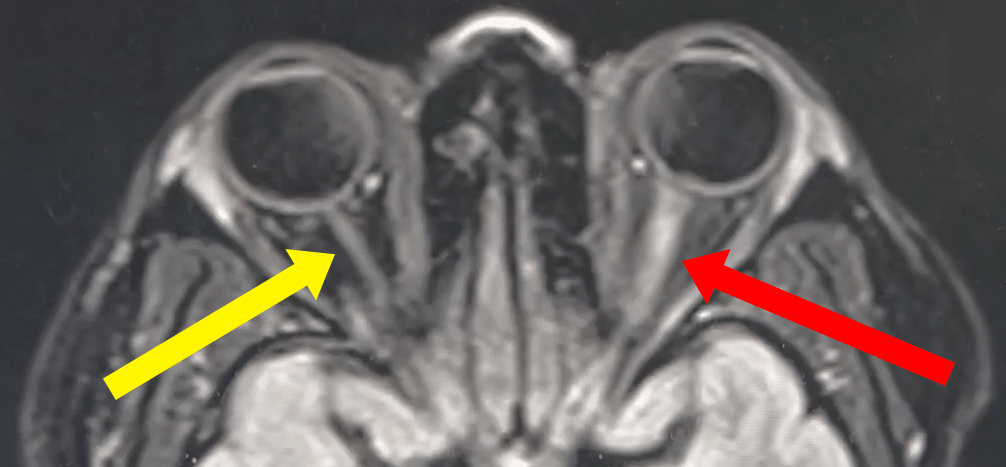

The red and yellow arrows in the image above point to the optic nerves. You don’t have to be a radiologist to appreciate that they are asymmetric. The red arrows points to the pathology.